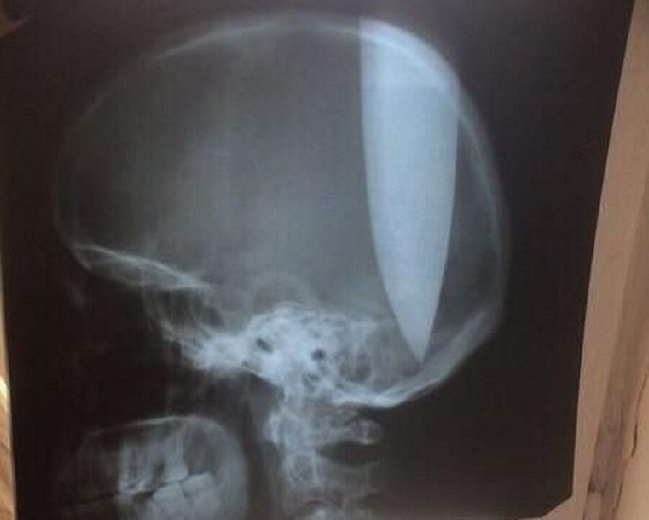

Alcanzó a enterrar 12 centímetros del arma en su propio cráneo.

Según consignó Daily Mail, el ruso se enterró el cuchillo 12 centímetros dentro de su cráneo y estuvo consciente todo el tiempo. Increíblemente no sufrió daño cerebral.